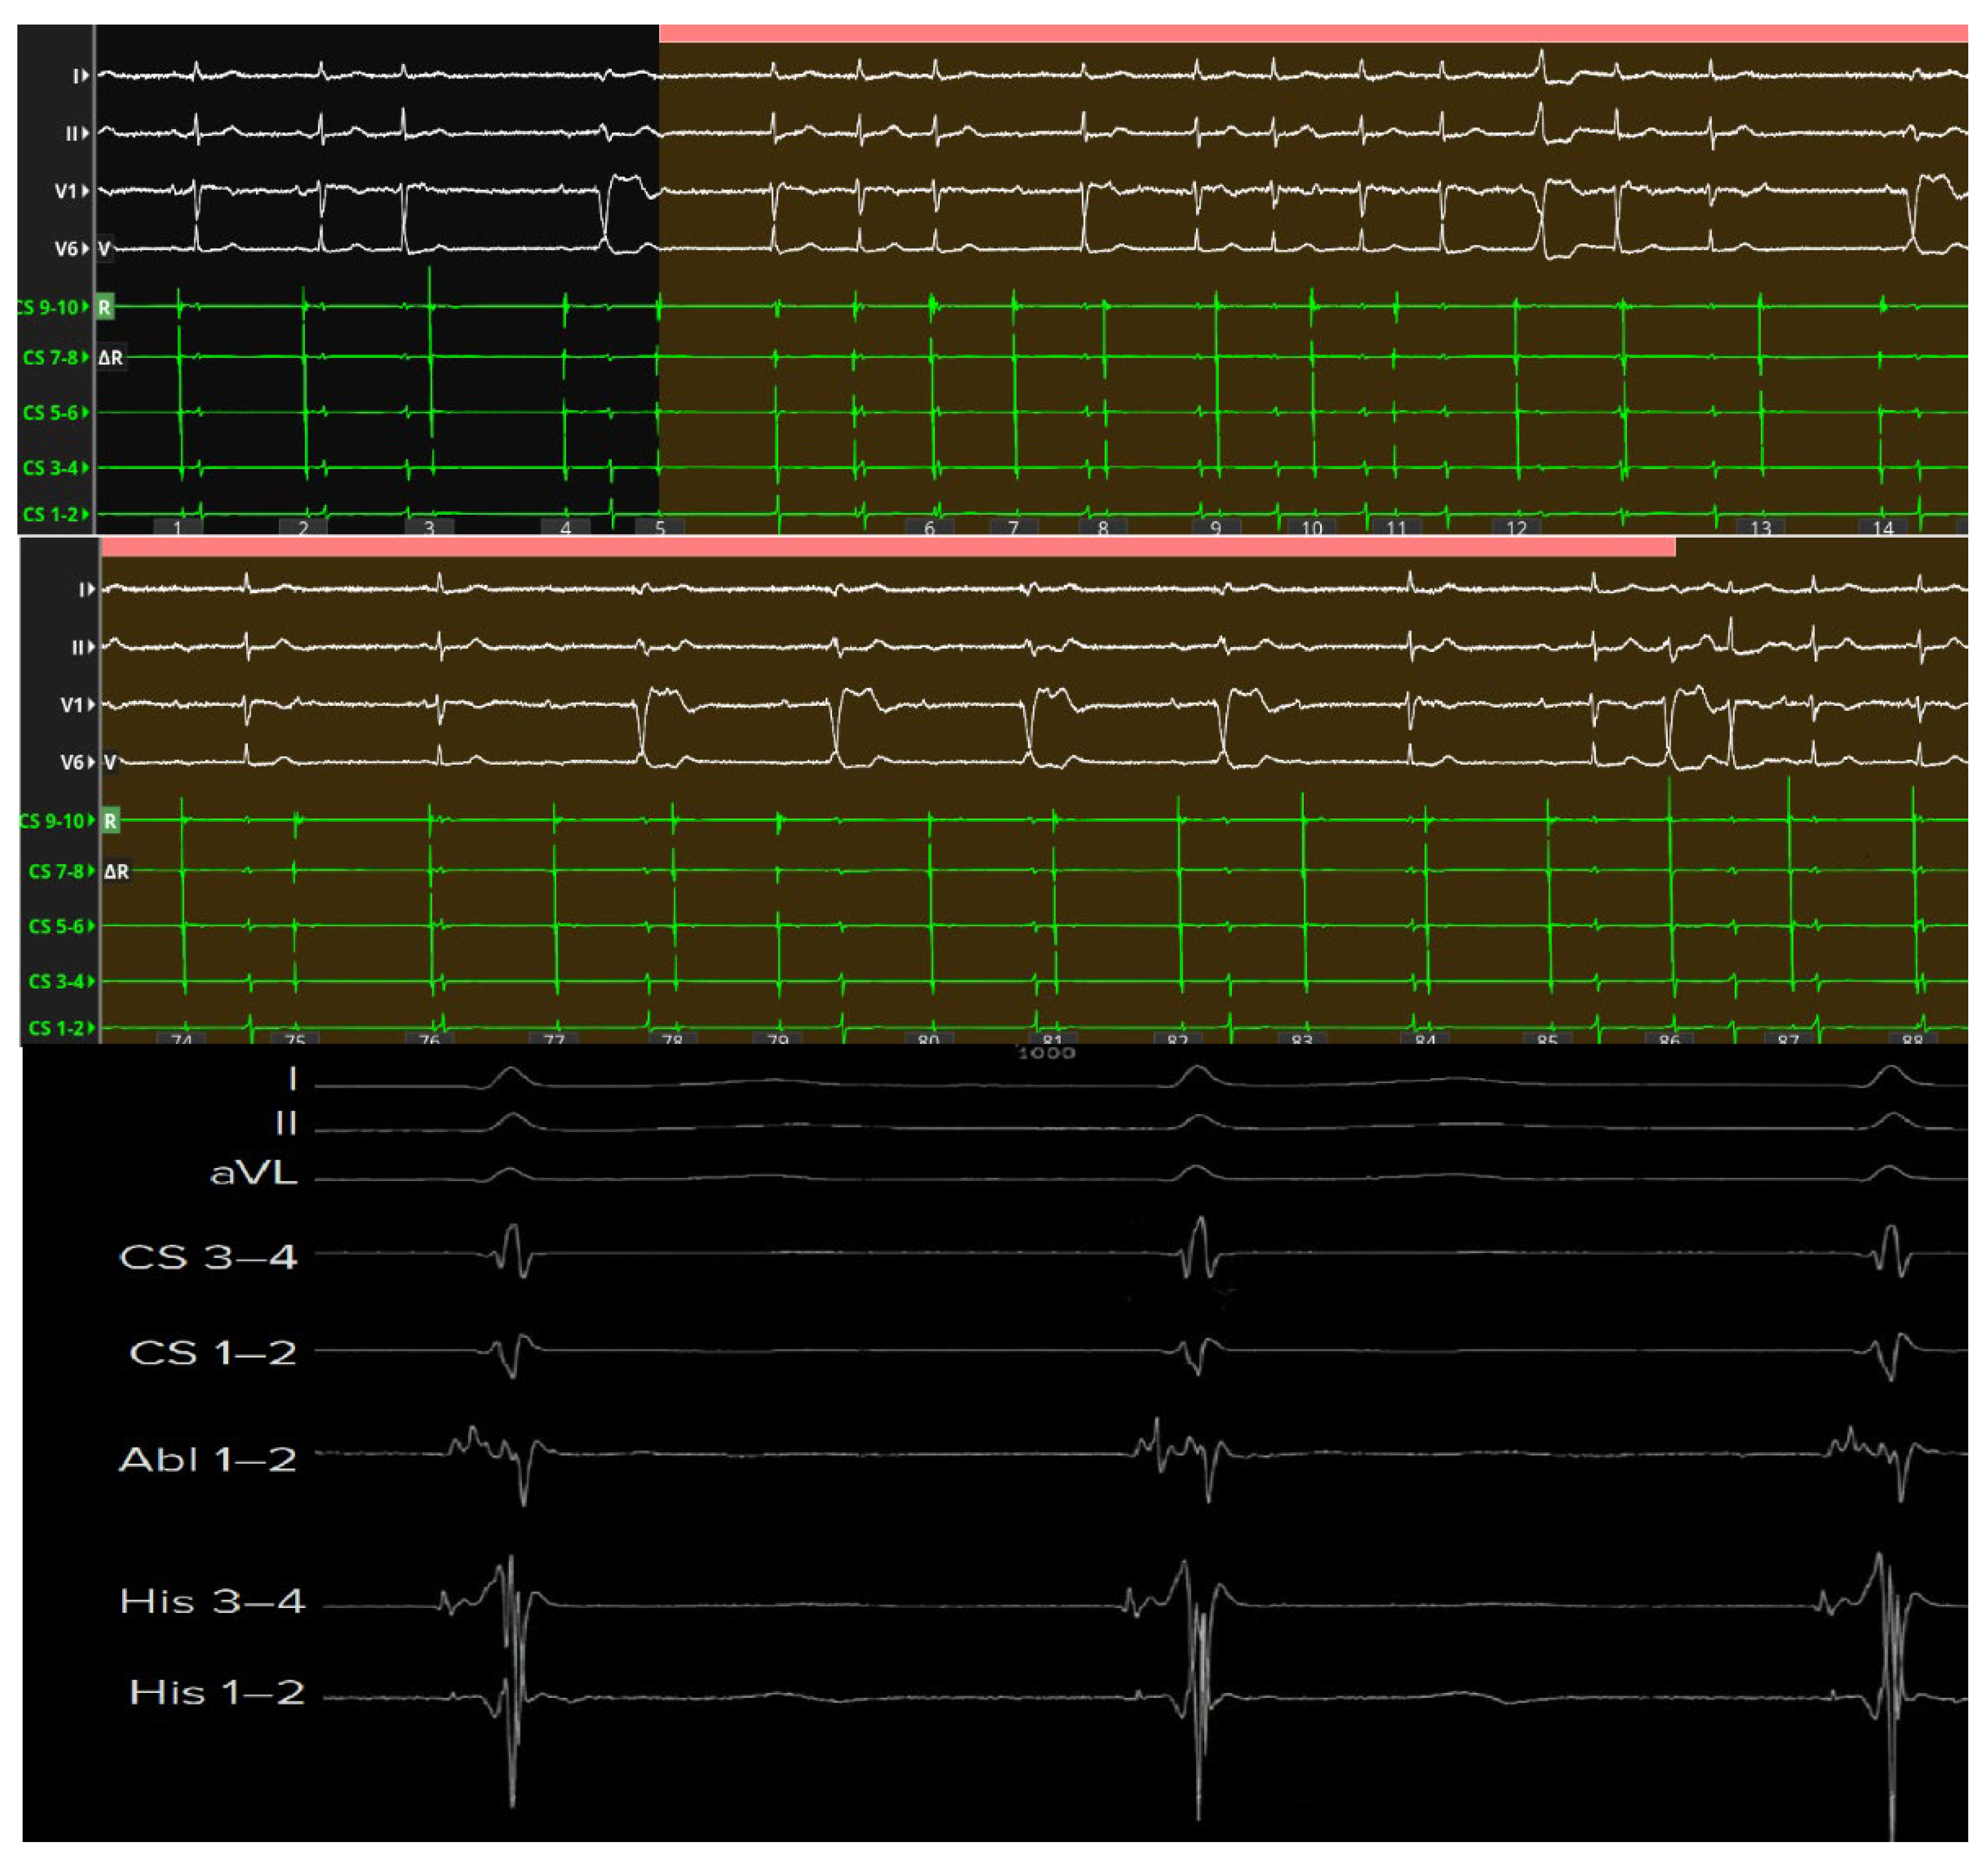

High-resolution mapping systems and specialized filtering settings, such as those used in our previous studies [30,31], may improve visualization of nodal potentials and enhance procedural precision. Using a catheter with small electrodes closely spaced from each other (0.4 mm2 area and 2.5 mm spacing) and an unconventional filtering of the bipolar electrogram (0.1–250) with high signal amplification, it is possible to appreciate the characteristics of AV node potential during both sinus rhythm and slow-fast AV node re-entry tachycardia. These characteristics are: (1) long—duration, low—frequency, low—amplitude AV node hump signal recorded by the electrodes overlying the AV node; (2) markable in the middle of AV node signal duration when no His activation is detected in the far field or at the beginning of His-like activation when this last is simultaneously recorded; (3) impossibility of recording this slow potential outside the Koch’s triangle; (4) recordable only in the mid—septal and posteroseptal regions of Koch’s triangle; (5) not observable after the blocked atrial electrogram during the Wenckebach sequences. Interestingly, the AV node potential had a significantly shorter duration and greater amplitude in sinus rhythm than in tachycardia, while during atrial stimulation, there was a widening and a decrease in the amplitude of the AV node potential. Furthermore, the AV node potential began before the high-frequency His deflection and ended after its offset during sinus rhythm, whereas during tachycardia, the AV node potential always preceded the onset of His deflection in the near field. By recording potentials in the posteroseptal region of Koch’s triangle (slow pathway region), it is possible to appreciate the AV node potential (low frequency and low amplitude) together with a high-frequency slow pathway Jackman potential, located just before the onset of the AV node potential (Figure 3).

Figure 3. Panel (A). Three-dimensional electroanatomical reconstruction of Koch’s triangle showing the spatial localization of the compact atrioventricular node (white star) immediately inferior to the His bundle region. The red star indicates the coronary sinus. Panel (B). High-fidelity intracardiac recording obtained with a high-density mapping catheter using bipolar filtering (0.1–250 Hz). The electrogram at the ablation site (bottom trace) exhibits the characteristic features of the compact AV nodal potential: a long-duration, low-frequency, low-amplitude “hump” deflection occurring between the atrial and His potentials (white arrow). This signal, confined to the mid- and posteroseptal portions of Koch’s triangle, precedes the onset of the His deflection and disappears outside this region, confirming its origin from the compact AV node. The simultaneous color-coded activation map demonstrates the anatomical relationship between the nodal electrogram and the surrounding structures, guiding precise lesion delivery while preserving distal conduction.